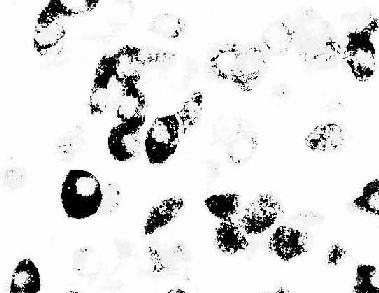

大鼠腺垂体免疫组织化学(PAS法)示生长激素细胞

图1-6 大鼠腺垂体免疫组织化学(PAS法)示生长激素细胞

(上海医科大赵培林教授供图)